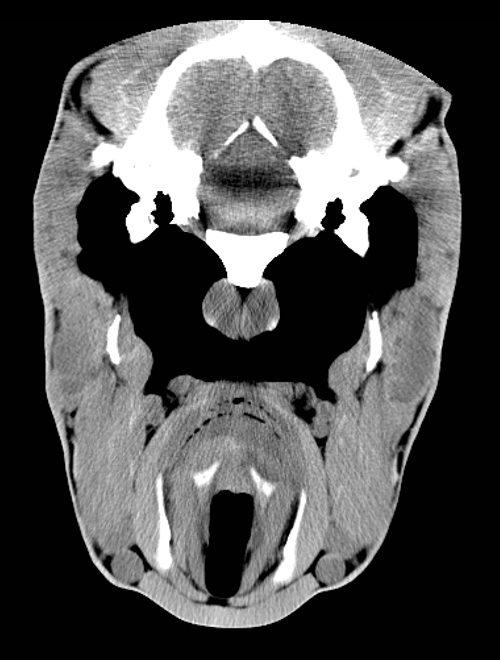

What is this artifact and how do we fix it?

What was the technique for reducing this artifact as suggested by Mosenco et. al (2004) for dogs and horses?

Porat-Mosenco, Y., Schwarz, T. & Kass, P.H. (2004) Thick-section reformatting of thinly collimated computed tomography for reduction of skull-base-related artifacts in dogs and horses. Veterinary Radiology and Ultrasound 45, 131–135